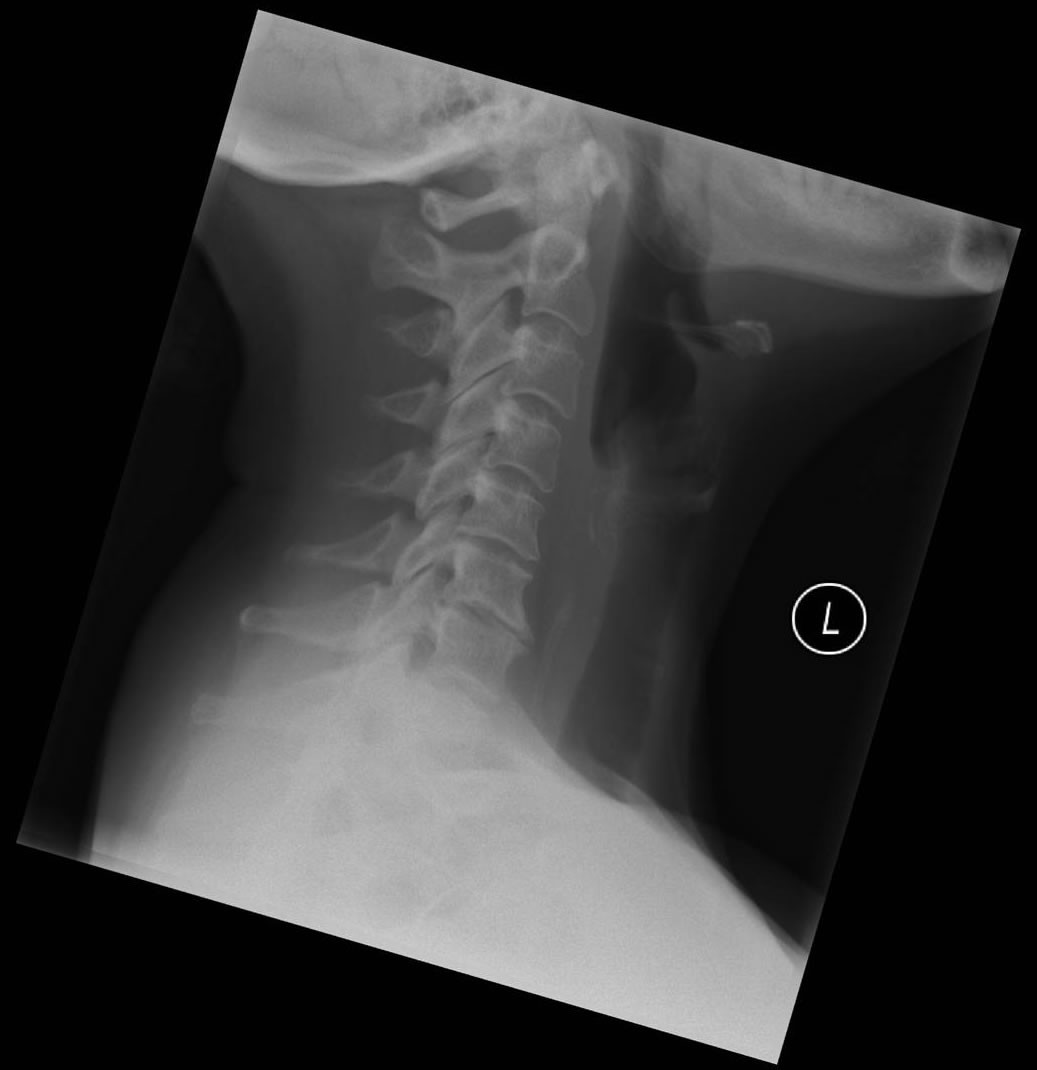

A pain in the neck!